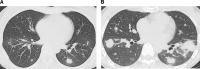

Actinomyces graevenitzii is a newly recognized Actinomyces species that is seldom isolated from clinical specimens. A case of multiple pulmonary abscesses mimicking acute pulmonary coccidioidomycosis is described in this study, and the findings indicate that this organism is an opportunistic human pathogen.